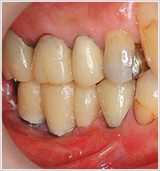

仮歯を装着しました。

この患者様は、上の歯もセラミックで治療していきます。

仮歯を入れて、かみ合わせ、発音、食事、見た目、歯ブラシの当て方などをチェックをします。

問題がなくなったところで、その仮歯を元にセラミックのかぶせ物を作ります。 - 治療完了・定期検診